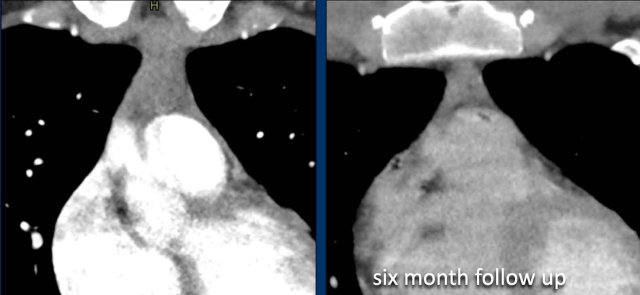

These images are of a 19-year-old man M19, who had a CT to rule out pulmonary emboli.

An incidental mass was seen in the prevascular space.

The most likely diagnosis was thymic hyperplasia and an MRI was performed to further differentiate this mass.

Continue with the MRI...

On the T2W-image the lesion was slightly intense.

On the out-of-phase image there wasn't much signal drop.

The SII was less than 9%.

Because the patient didn't have any complaints and especially no symptoms that could be associated with lymphoma and because a thymoma is a rare tumor, it was decided to do a six months follow up.

At six months follow up there is a normal thymus.

It was concluded that this was thymus hyperplasia or a large thymus rest, which involuted during the six months.